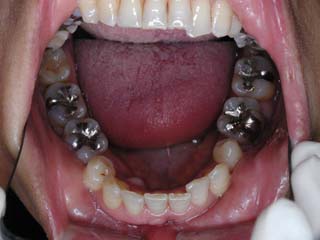

主訴:上の歯が出ている

診断名:顎関節症、上顎前突、叢生を伴う開咬

年齢:20歳

使用した主な装置名:TPB、マルチブラケット装置

抜歯/非抜歯および抜歯部位:抜歯(上顎左右第一小臼歯、下顎左右第二小臼歯)

治療期間:動的処置2年3か月、経過観察3年

費用の目安:保険適応 自己負担金として30~50万

リスク、副作用:外科手術によるリスク、マルチブラケット治療に伴う歯根吸収など偶発症が発生するリスクがある。

比較的強い叢生と、下顎の劣成長を伴う開咬が見られます。成長を終了した永久歯列ですので、骨の大きさのズレへのアプローチは大きく別れる所です。程度が小さければ、歯の傾きで補うように解決しますし、大きなズレであれば、外科的に骨のズレを改善する治療が選択されます。垂直的な問題はその他の不正咬合と比較して、解決が極めて困難な事が多いです。治療後の後戻りが頻繁に見られる不正咬合ですので、外科矯正での改善が望ましい場合も多いでしょう。

術前矯正の仕上げにスプリント治療を行った方が良い場合が多いです。現在、当院での治療では、術前に3か月のスプリント治療を必須にしております。せっかく手術までしてかみ合わせの位置を合わせようとしているのに、顎の関節の位置がずれていたらどうなるでしょう。顎の関節は往々にして顎の大きさのズレをカムフラージュするような偏位を示すので、術後にじわじわと後戻りしているような現れ方で、ズレが見えてくるのでは?このスプリント治療を徹底できたケースでは術後の安定性が極めて高いと感じています。

外科手術は、上顎のインパクションのみをLeFort1にて行いました。